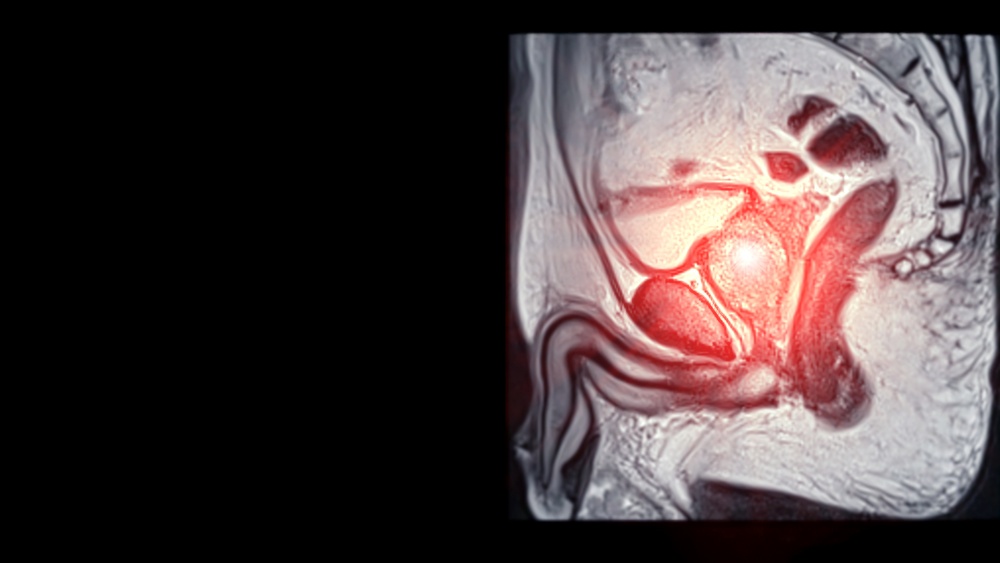

A IA usada foi a desenvolvida no consórcio PI-CAI, construída a partir de um conjunto grande (mais de 10 mil exames bpMRI no estudo original). A saída da IA incluía um mapa de detecção de lesão (tipo mapa de calor sobreposto à sequência axial T2) e um score global por paciente. Para facilitar a interpretação, eles recalibraram o score em escala 1 a 10, onde 10 indica maior probabilidade de câncer clinicamente significativo. Essa recalibração foi feita usando 420 exames holandeses (coorte de calibração), e os 360 exames do estudo formaram a coorte de teste, incluindo um centro norueguês externo aos holandeses.

Os exames foram bpMRI com T2 em três planos e difusão com b alto e mapa ADC, feitos em aparelhos 1,5T e 3T, de dois fabricantes (predomínio de Siemens). Esse detalhe parece técnico, mas é importante, pois algoritmos podem performar de forma diferente quando muda fabricante, protocolo, ruído, bobina, qualidade de imagem.